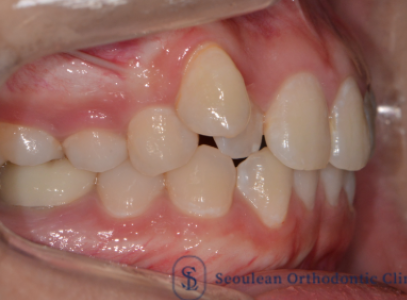

분당교정치과|10대 남학생 골격성 2급·돌출입, 제2소구치 발치교정으로 자연스러운 안모 개선